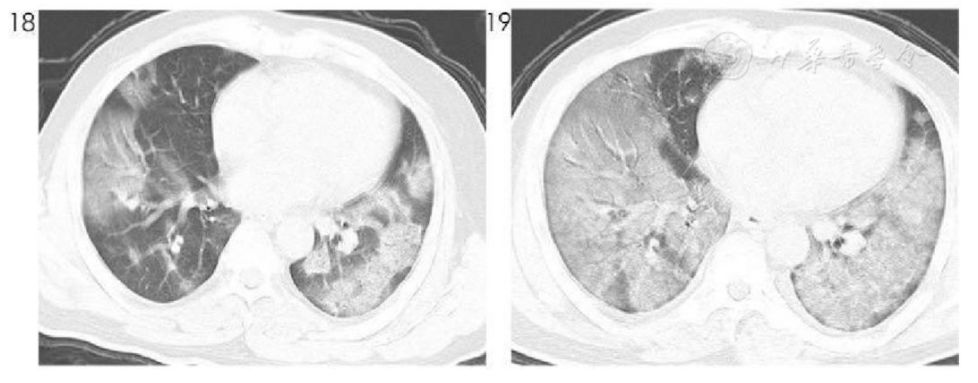

实战演习

胸部CT如下,先后4次咽拭子核酸检测均为阴性,要不要执着地考虑新冠肺炎?

图26

CT表现非常典型,不能轻易放弃!给予高渗盐雾化诱导排痰后,痰标本送检,结果显示新型冠状病毒核酸检测阳性,氧合指数为276 mmHg,最后确诊为新型冠状病毒肺炎重型。